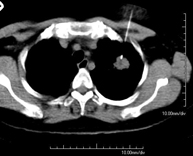

- TC Tórax

Prueba diagnóstica que consiste en obtener imágenes del tórax de alta definición anatómica (pulmones, corazón, mediastino, grandes vasos, caja torácica, etc.) mediante el empleo de un equipo de TC (Tomografía Computarizada). Dichas imágenes se estudian posteriormente en una estación de trabajo que permite reconstrucciones bidimendionales en diferentes planos del espacio y también reconstrucciones 3D (volumétricas). Algunos estudios requieren el empleo de contraste yodado para mejorar la definición de las imágenes. - Angio-TC Aorta torácica